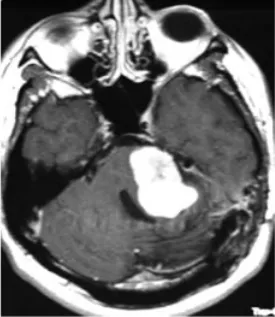

随后,患者再度出现面部麻木感与共济失调症状。此次磁共振检查结果令人警惕:肿瘤体积出现了显著扩大。临床团队判断肿瘤的生物学行为已发生根本性改变,遂实施根治性切除手术。

术后病理报告带来了最坏的消息:肿瘤已转化为恶性外周神经鞘膜瘤。免疫组化染色结果显示,此前在肿瘤细胞中呈弥漫阳性分布的S100蛋白,此时已变为仅灶性阳性,提示肿瘤细胞正在经历去分化过程。

然而恶化的速度远超预期。根治性切除手术后不过三个月,肿瘤即以极强的侵袭性迅速复发,并对脑干造成严重压迫。为维系基本生命功能,患者紧急接受了第二次手术以实施脑干减压。这一次的病理结果表明,肿瘤已进一步去分化,转化为间变性软组织肉瘤,神经源性标记物S100蛋白的表达已完全丧失。